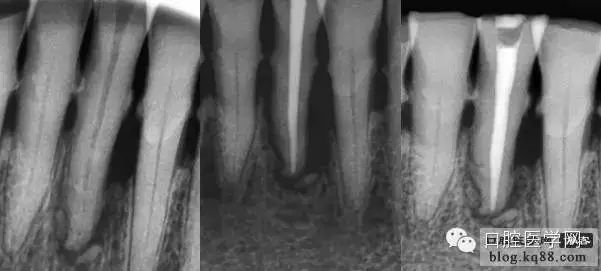

試好后的主尖經(jīng)X片評價合適后要放入2.5%的次氯酸鈉中消毒備用,一般3分鐘就可以達(dá)到消毒標(biāo)準(zhǔn),然后充填時用氣槍吹干,不能用棉球或紗布擦。